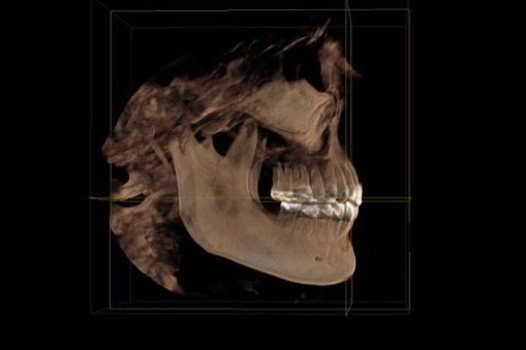

Over 40 million Americans suffer from Myofascial Pain Dysfunction (MPD), a condition that causes headaches and muscular pain. Dr. Klim uses advanced biofunctional diagnostic techniques to decrease painful tension in the head, neck, and shoulder muscles.

Many suffer from Myofascial Pain Dysfunction (MPD) and are not sure of the nature of their condition and how to solve it. You may have heard other terms that describe this condition such as TMJ or TMD. This is short for Temporomandibular Joints. Craniomandibular Dysfunction (CMD) or Temporomandibular Disorder (TMD) are another terms dentist use.